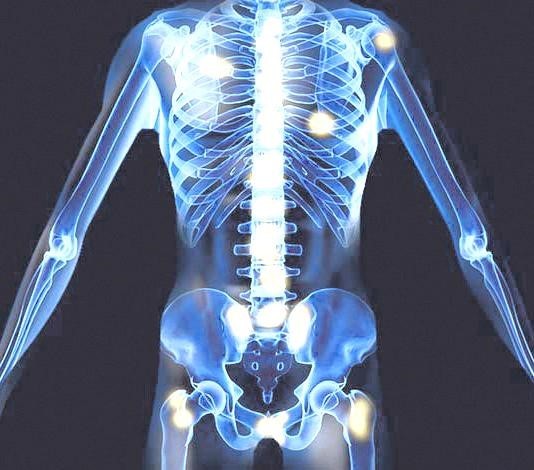

10. 전립선암 뼈전이

전립선암은 뼈로 잘 전이됩니다. 전립선암이 뼈로 전이되면 전이된 부위에서 통증이 발생하게 되며, 그 부위가 약해지면 골절이 생길 수도 있습니다. 전립선암 뼈전이는 주로 골반뼈, 요추, 흉추 등으로 전이되는 그럴 경우가 많습니다.